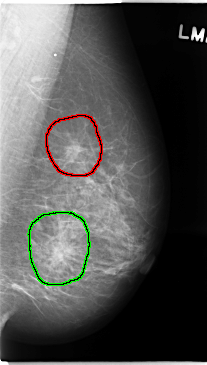

C_0137_1.LEFT_CC

LEFT_CC LINES 4744 PIXELS_PER_LINE 2528 BITS_PER_PIXEL 12 RESOLUTION 50 OVERLAY

FILE: C_0137_1.LEFT_CC.OVERLAY

TOTAL_ABNORMALITIES 1

ABNORMALITY 1

LESION_TYPE MASS SHAPE ARCHITECTURAL_DISTORTION MARGINS SPICULATED

ASSESSMENT 5

SUBTLETY 5

PATHOLOGY MALIGNANT

TOTAL_OUTLINES 1

BOUNDARY